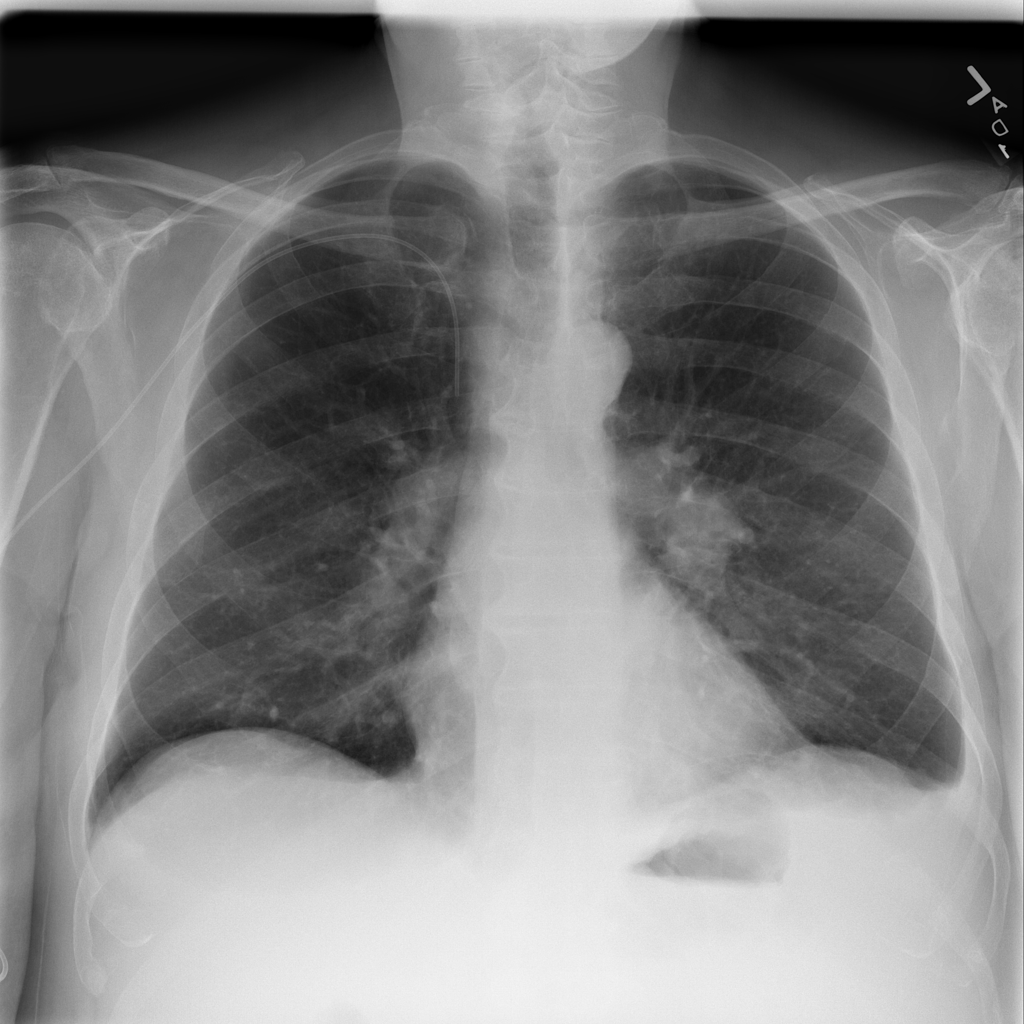

PAT-C0E5 · IMG-001Mass

PAT-C0E5 · IMG-001

PA